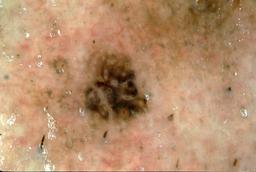

{

"age_approx": 75,

"anatom_site_general": "head/neck",

"concomitant_biopsy": true,

"dermoscopic_type": "contact non-polarized",

"diagnosis_1": "Malignant",

"diagnosis_2": "Malignant melanocytic proliferations (Melanoma)",

"diagnosis_3": "Melanoma, NOS",

"diagnosis_confirm_type": "histopathology",

"image_type": "dermoscopic",

"lesion_id": "IL_4116158",

"melanocytic": true,

"patient_id": "IP_4497472",

"sex": "male"

}